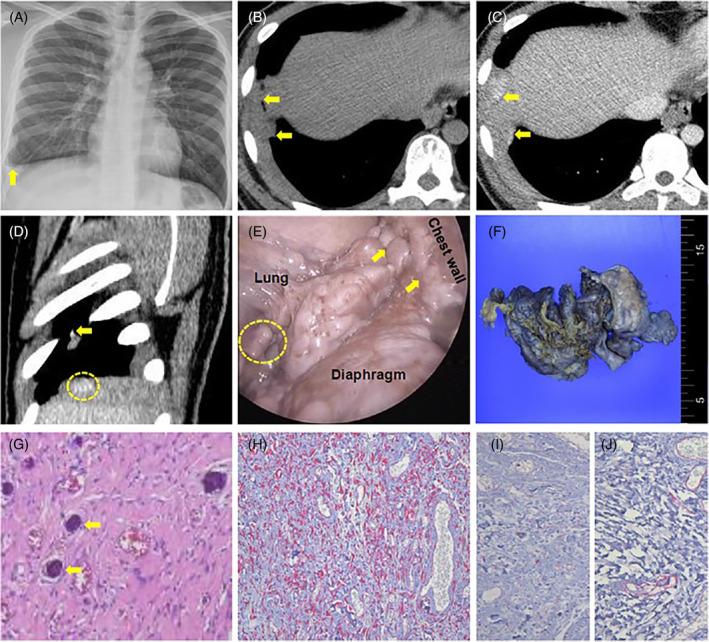

Calcifying fibrous tumour of the pleura without gross calcification.

Calcifying fibrous tumours of the pleura (CFTP) typically appear as calcified, non-enhancing lesions on chest CT scans. However, enhancing pleural lesions can mimic malignancy like mesothelioma. We report a rare case that enhancing pleural thickening, confirmed as CFTP through pathological examination, despite the absence of visible calcification on radiological imaging.

胸膜钙化性纤维瘤(CFTP)在胸部CT扫描中通常表现为钙化的、无强化的病变。然而,强化的胸膜病变可能会模仿间皮瘤等恶性肿瘤。我们报告一例罕见病例,尽管影像学检查未见明显钙化,但经病理检查证实为CFTP的强化性胸膜增厚。